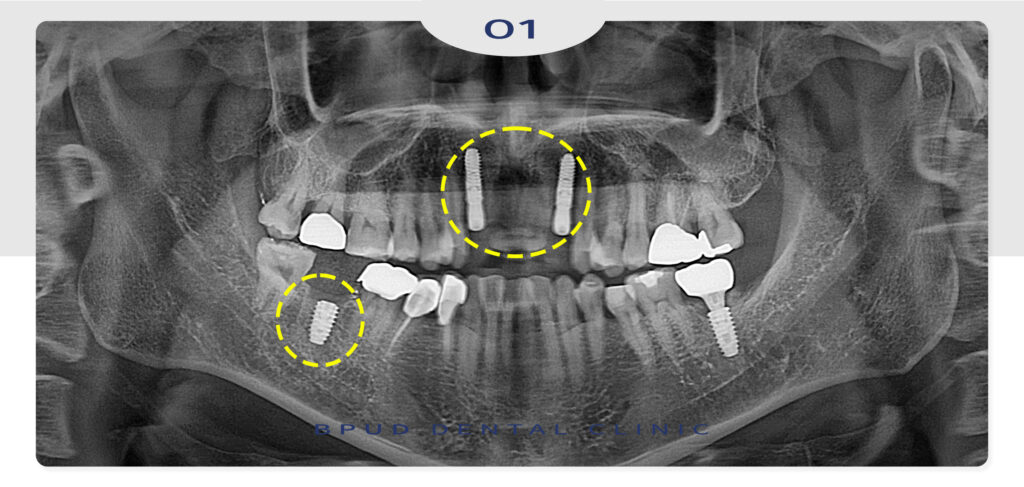

최종 보철물을 완료한 후의 사진입니다.

최종 보철물 합착 전, 임시치아를 미리 제작하여

환자분과 함께 모양과 형태에 대한 이야기를 충분히

나눈 뒤, 보철물을 제작하여 매우 만족해 하셨는데요.

오랫동안 콤플렉스였던 것을 해결하셨다며

아래 앞니 부위도 추후 진행하시겠다고 하셨습니다!